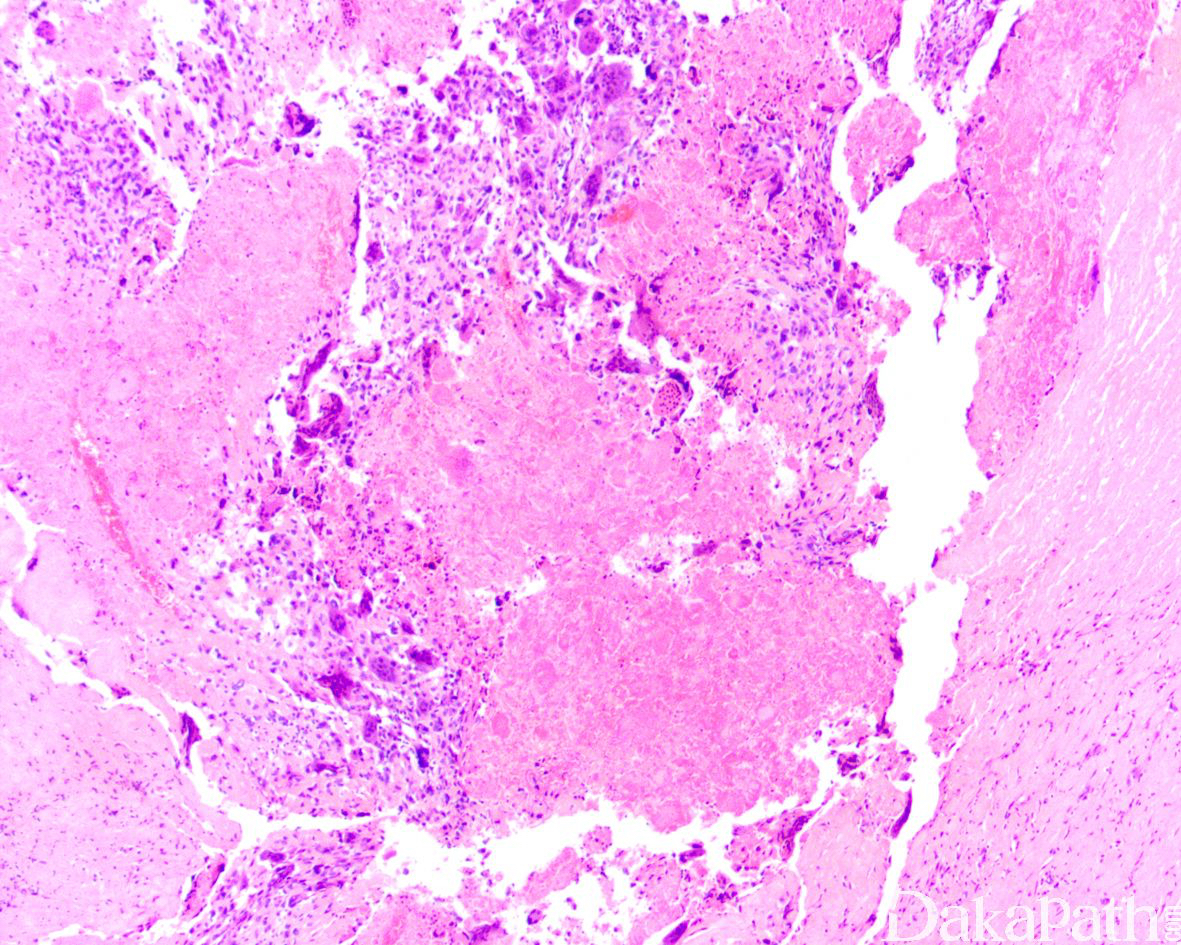

形态学与其他特殊类型的多形性肉瘤很相似,无一定的排列方式,常伴奇异的多核瘤巨细胞。

大体检查呈孤立性、多分叶状、鱼肉样棕白至灰色的肿块,常见出血和坏死区域;

镜下细胞丰富,可见席纹状结构;

特点为大的多形性细胞,伴有大而深染的细胞核和明显的核仁;

大量核分裂象,常见非典型性核分裂象;

可见玻璃样变和坏死区域,也常见黄色瘤细胞;